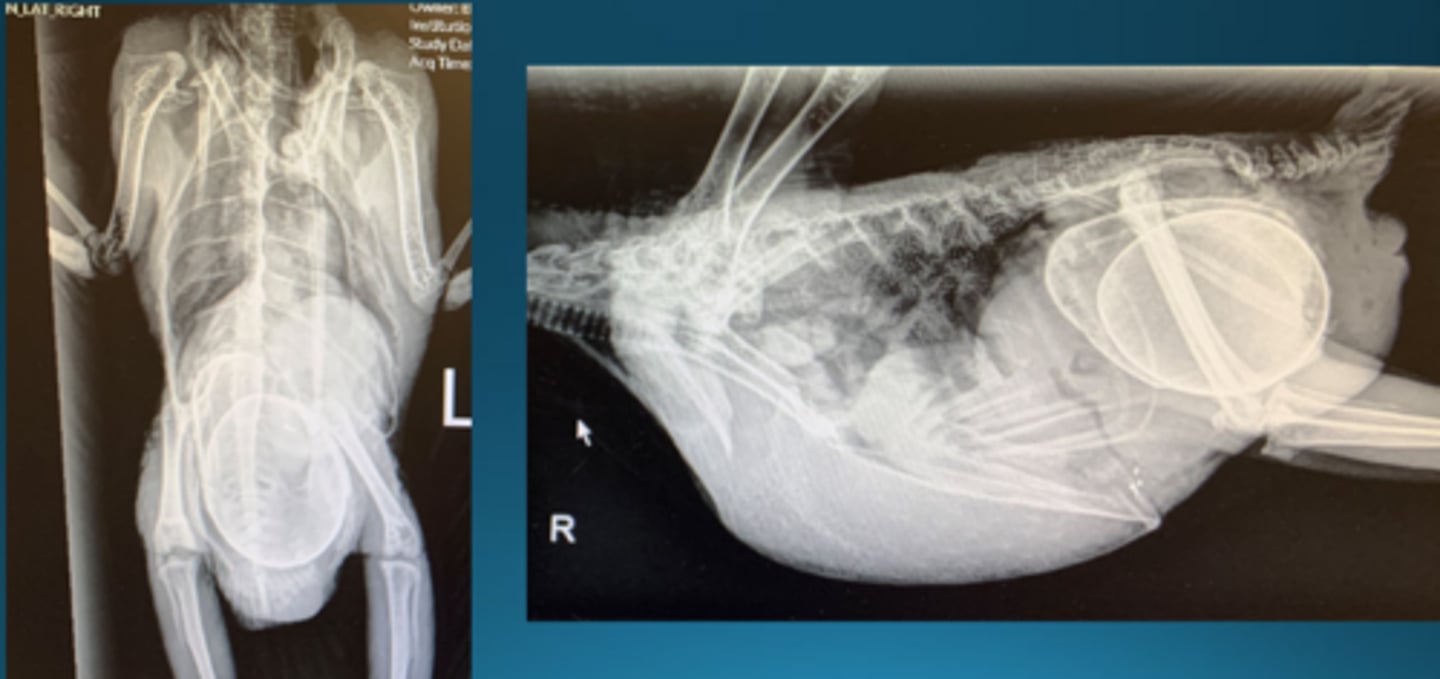

1. ostotic hyperostosis of the radius and ulna = physiologic, mostly normal for repro process under influence of estrogen

2. egg telescoped inside another in the caudal region of the coeloem

3. coelomic enlargement, more fluid than expected

4. especially visible on VD, soft tissue mass on lateral side around the level of the pelvis

Describe some things you see in this bird